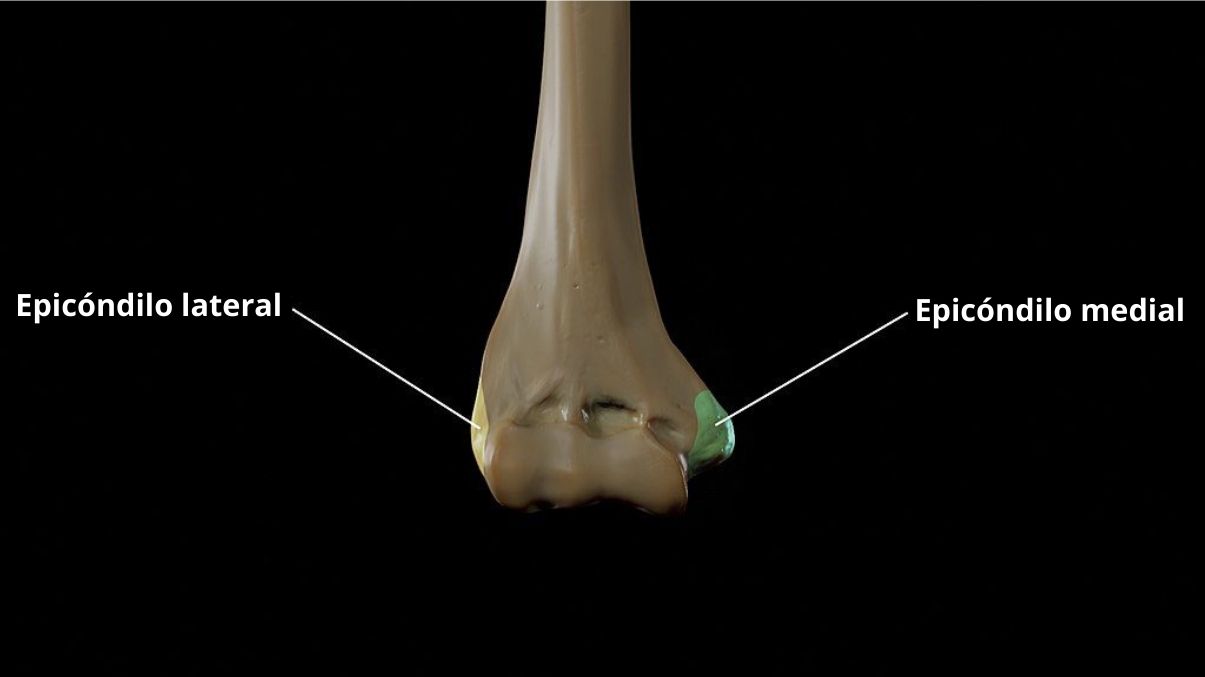

Epicondyle / Medial Epicondylar Fractures Of The Humerus

RiT radiology Medial Epicondyle Fracture of the Humerus

Epicóndilo concepto, características, funciones y patologías